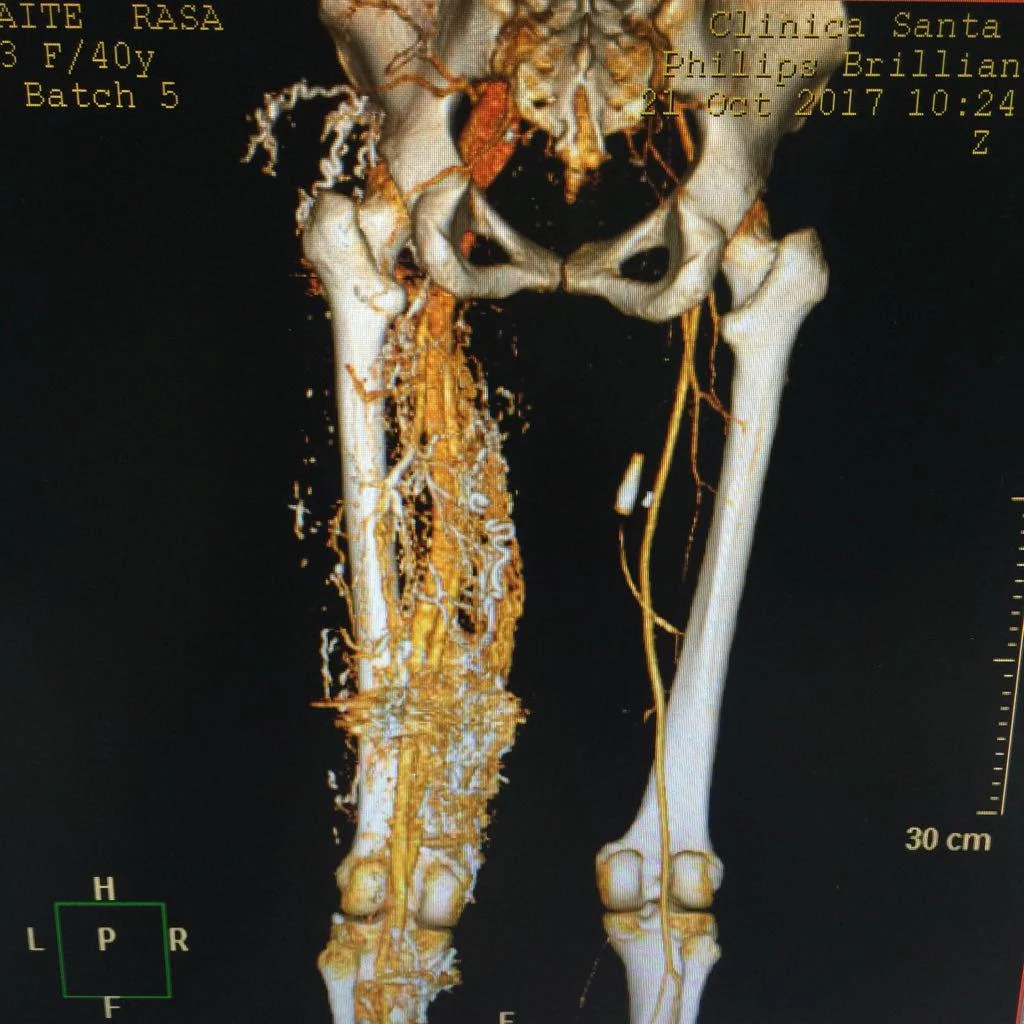

A CT scan of Rasa’s left leg

Being that her condition is hidden, she says no one would ever know unless she showed them her CT scan. “As I don’t show my leg in public, no one knows, unless I show them the MRI photograph. However, she adds that for years, her scarring left her with little self-confidence.